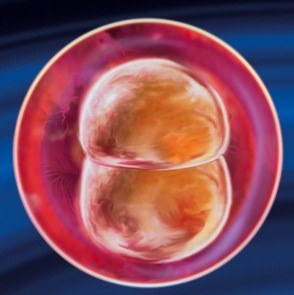

Говорити про те, як виглядає плід на 2 тижні ще рано, тому що його фактично не існує, в цей період тільки виникають передумови для його появи. Зараз це всього лише яйцеклітина, готова зустрітися зі сперматозоїдом і почати свій шлях в матку. На фото показаний процес овуляції.

Ще деякий час зародковий диск буде оточений оболонкою, яка його живить, але незабаром клітини стануть нерівномірними і розділяться на дві групи: перша дасть початок майбутньої плаценті, а друга - тілу зародка. З цього моменту починається ембріональний етап розвитку майбутньої дитини, він буде тривати 10 тижнів. Однак ризик викидня на цьому етапі дуже високий, і це пояснюється простими законами природи: якщо стався збій при закладці життєво важливих органів малюка, то організму жінки простіше відкинути ембріон, поки він ще крихітний саме на початку вагітності, а не в середині.